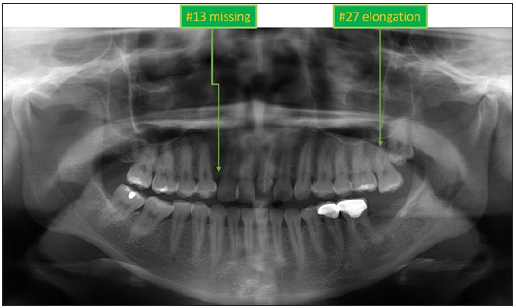

ovoid shape (Figure 1). Panoramic findings showed #13 missing and #27 elongation (Figure

2). Cephalometric analysis indicated that this patient had a skeletal. Class I pattern with

Figure 2:Initial Panoramic radiograph.